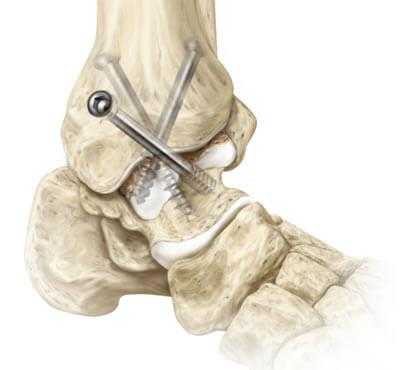

Артродез голеностопного сустава: виды замыкания, показания, осложнения

Артродез голеностопного сустава - оперативное вмешательство по искусственному сращению сочленяющихся суставных поверхностей голеностопа в физиологически выгодном для функционирования ноги положении. Основной целью хирургического лечения является придание опоропрочности проблемной зоне посредством полного блокирования ее подвижности (создания анкилоза). Обездвиживание достигается за счет жесткого соединения примыкающих концов костей сустава между собой специальными фиксаторами из металла (спицами, винтами, штифтами и пр.). Это позволяет прочно срастись суставным поверхностям друг с другом под нужным углом, то есть, привести сочленение в полное неподвижное состояние, что поможет пациенту избавиться от сильной боли и нестабильности стопы.

- Внутрисуставный. В процессе хирургии выполняется вскрытие капсулы сустава с последующим удалением поврежденного гиалинового хряща с поверхностей костных элементов. После репозиции костей в выгодном положении выполняется их фиксация металлическими приспособлениями.

- Компрессионный. Операция заключается в сдавливании сочленяющихся поверхностей аппаратом компрессионного или компрессионно-дистракционного типа для дальнейшего их сращения. Широко применяемые конструкции - аппараты Илизарова, Гришина, Волкова-Оганесяна. Удаление хряща не исключается. Вживление костного трансплантата для способа компрессии не требуется.

- На нижнюю треть бедра накладывается пневматический жгут. Далее создают доступ, совершая скальпелем линейный кожный разрез вдоль сустава. Разрез равен примерно 10 см.

- На следующем этапе выполняется вскрытие и надежная супинация сустава, которая облегчит работу с очередными манипуляциями.

- Затем подготавливаются поверхности большеберцовой и таранной костей. Подготовка включает резекцию хрящевых тканей хирургическим долотом, удаление окостенения.

- Дальше стопа выводится из порочного положения. Большеберцовый элемент и таранный компонент плотно сопоставляют друг с другом в удобной с точки зрения физиологии позиции. Достигнутая позиция скрепляется металлической конструкцией необходимого типа.

- Используемые операционные ходы на завершающем этапе закрывают при помощи послойного ушивания мягких тканей с оставлением дренажа.